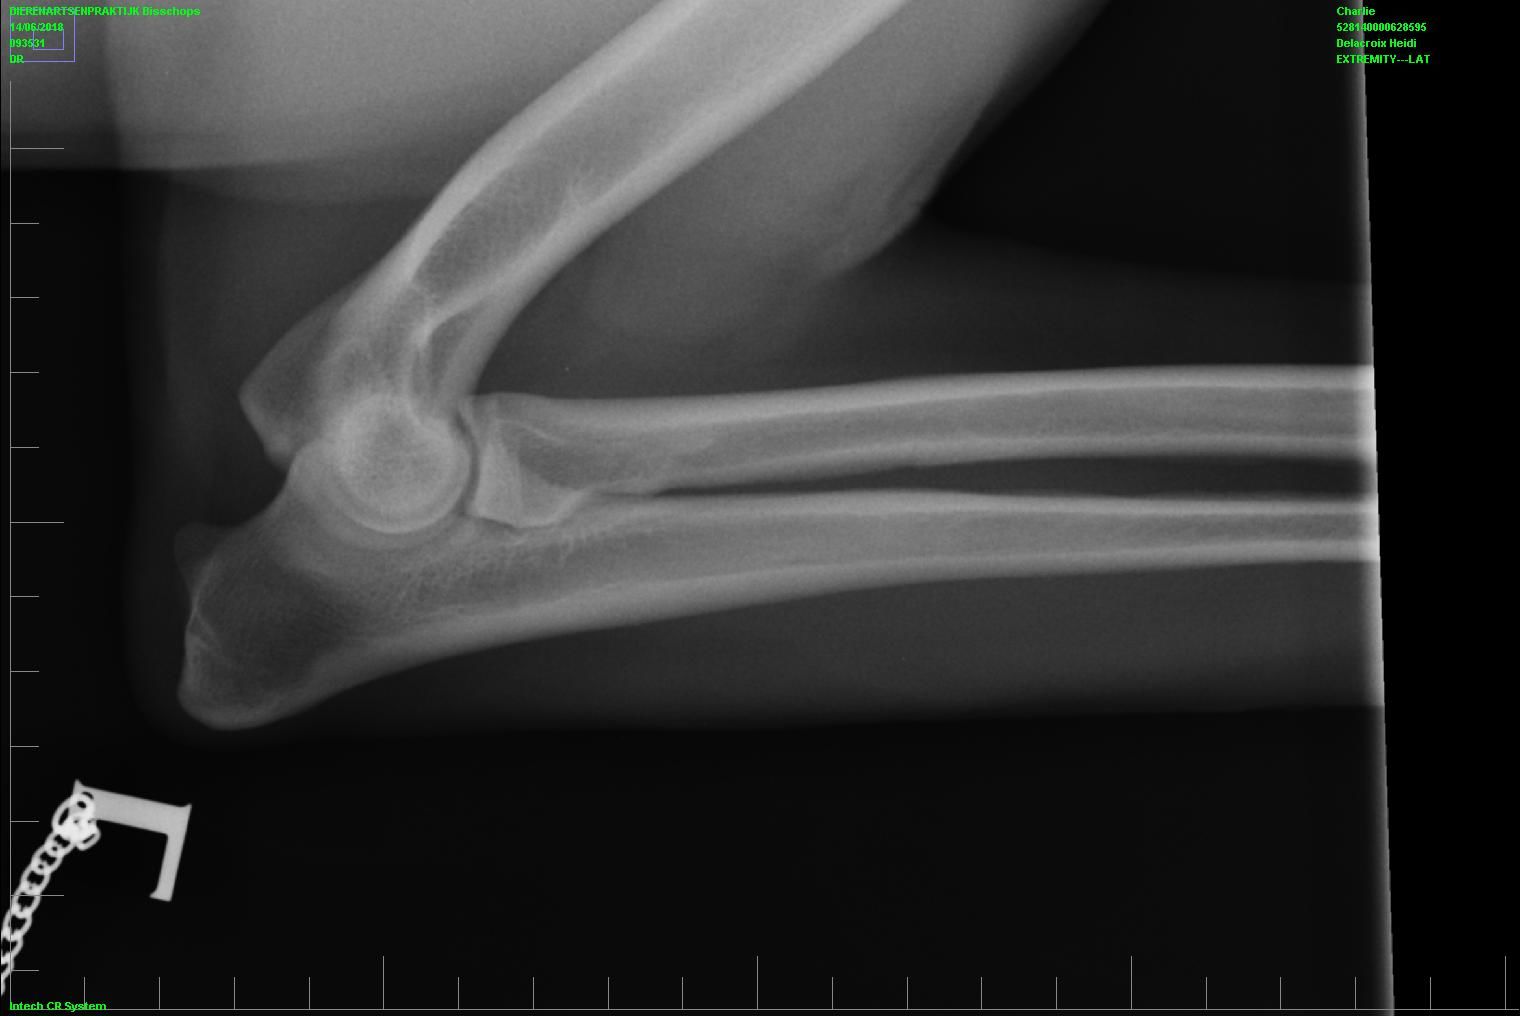

• heupen (kwalificatie A , Norberg L106 R103)

• ellebogen (kwalificatie 0 )